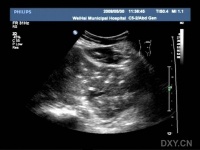

B超为无创性检查,方便易行,是肝内胆管结石诊断的首选方法,一般估计诊断准确率为50%-70%。肝内胆管结石的超声图象变化较多,一般要求在结石远端的胆管有扩张才能作出肝内胆管结石的诊断,因肝内管道系统的钙化也具有结石样的影像表现。

肝内胆管结石的诊断不受肠道气体的干扰,诊断的准确性优于肝外胆管结石。诊断正确率70%~80%。但肝内胆管分支较多,不仔细扫描易漏诊,而且还要与肝内钙化点相鉴别。B超对肝内钙化点与肝内胆管结石鉴别困难在于,如果肝内点状、团状回声,其后若有声影,并不是典型的条索状回声,其后拽有声影,那么单纯依靠B超诊断肝内胆管结石比较困难。应结合其它手段综合判断。

B超诊断肝内胆管结石典型的图像是条索状回声,其后拽有声影,其远端胆管明显扩张,可为结石引起的胆道梗阻及并发的胆管狭窄所致。有报道术中B超的应用(术中于肝脏面、膈面全面超声扫描)可提高肝内胆管结石的诊断率达91%,残石率降至9%。